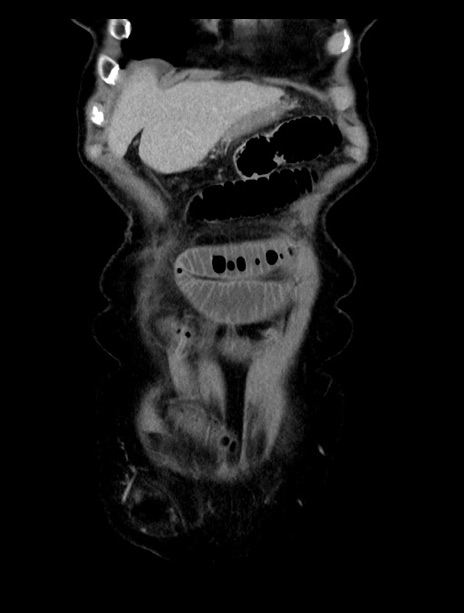

症例23(冠状断像)

【症例】70歳代女性

【主訴】下腹部痛・嘔吐

【現病歴】2日前より腹痛あり。昨日嘔吐あり。症状改善しないため来院。

【既往歴】胃GISTに対して胃部分切除後。

【身体所見】BT 37.1℃、BP 128/77mmHg、腹部:平坦・軟、下腹部に圧痛あり。

【データ】WBC 10200、CRP 0.31

横断像